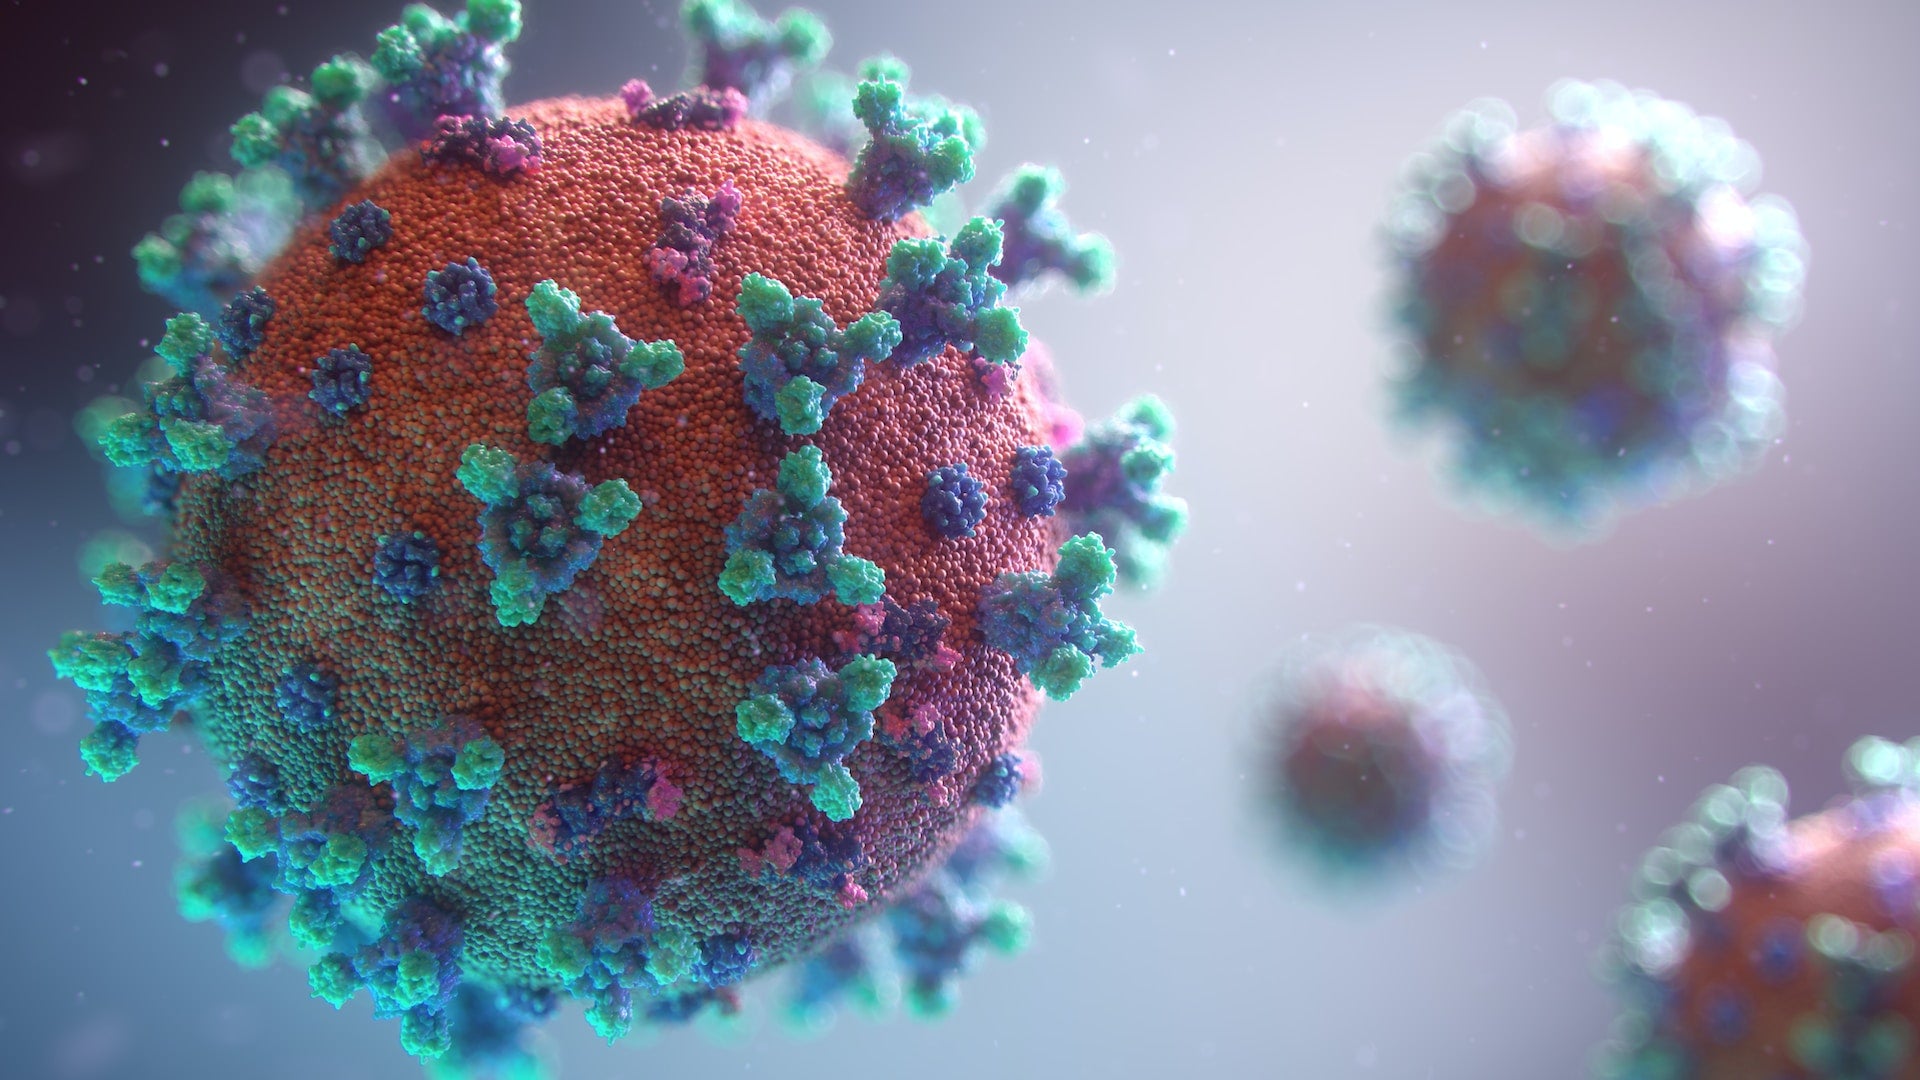

Read moreWhat You Should Know About Sleep Apnea and Long COVID

COVID-19 no longer dominates the headlines like it used to — but for people with obstructive sleep apnea, this doesn’t...